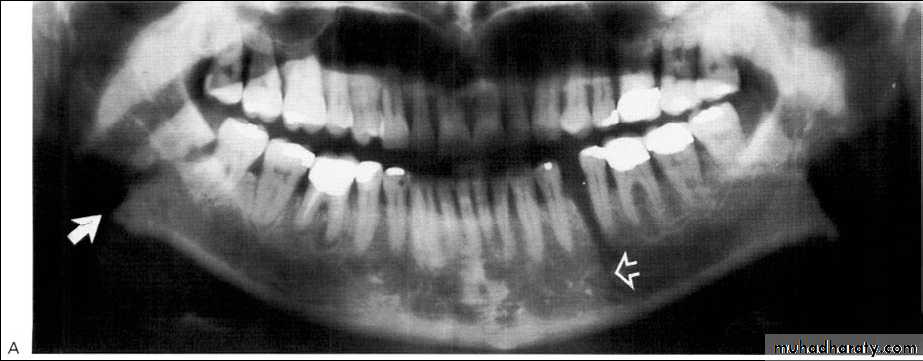

*Hereditary & involve many members of the family.*Age; <20 years.

*Affect the jaw bone only.

*Bilateral, expansile, multiple, soap bubble-like radiolucencies in the mandible.

*Migration of teeth & tooth germ, without exfoliation or become loosed.

5-year-old boy showing the typical bilateral multilocular lesions of

cherubism affecting the mandible (arrowed).Multiple but separate radiolucent lesions